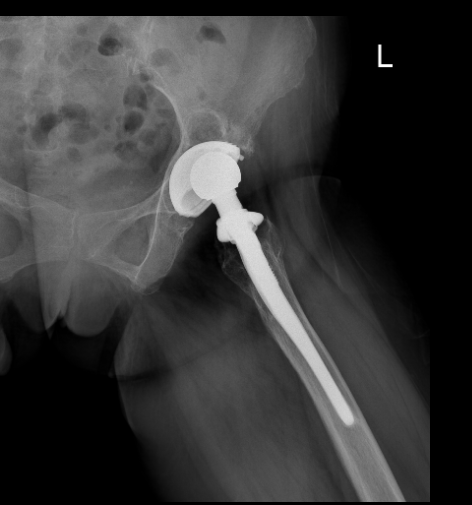

追溯病史可知,患者 20 余年前因股骨头坏死接受左侧全髋关节置换术,术后初期恢复良好,但随着假体使用年限增长,逐渐出现关节磨损与脱位,近半年症状显著加重。

影像学检查提示,其所用假体为 2001 年的产品,因技术迭代已停止应用,且存在髋臼严重缺损(术中可见 "陨石坑" 样骨缺损)及臀中肌完全缺失等复杂情况。